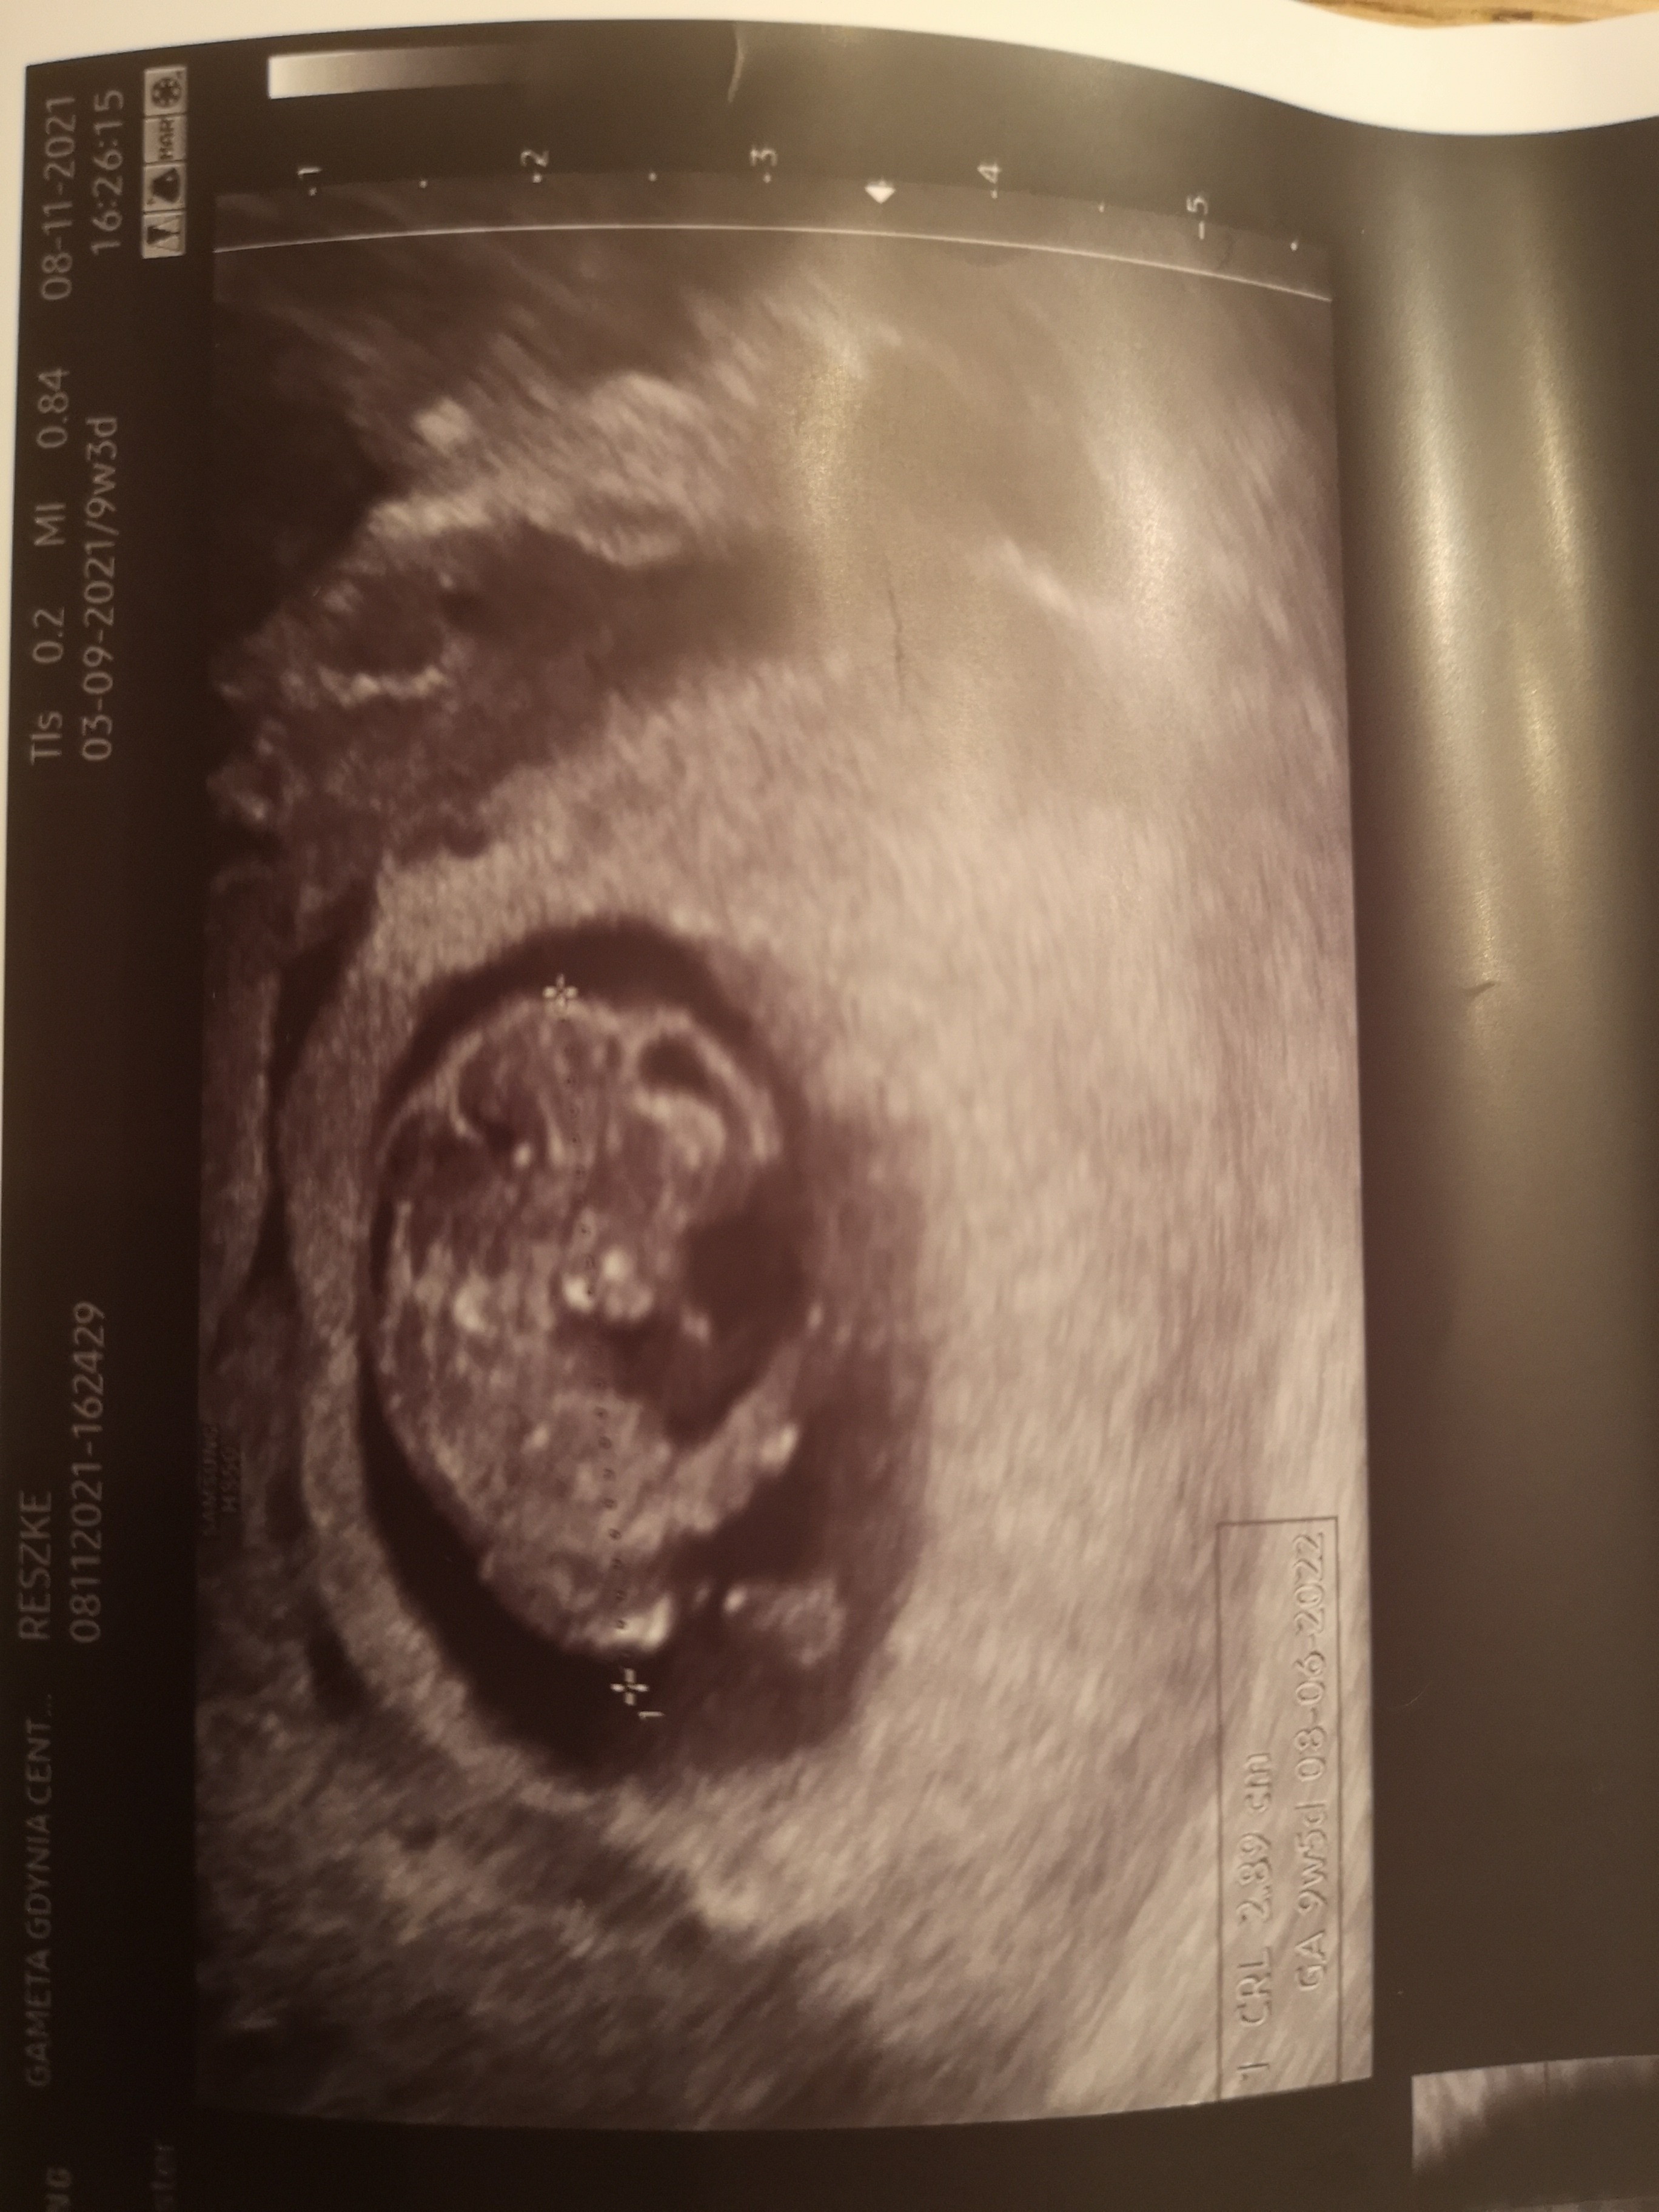

A to Malenstwo, zdjecie z wczoraj.

W ogole bardzo sie wczoraj zdenerwowalam, bo wyszedl mi tragiczny wynik tsh - mam wycieta tarczyce z powodu raka-wiec bazuje tylko na euthyroxie. Zawsze wynik oscylowal mi w granicach 0,5, a wczoraj, po trzech tygodniach mialam 7,5! Oczywiscie z nerwow sie poryczalam w gabinecie, ze to bardzo zaszkodzilo dziecku, ale gin mnie uspokoil (jest tez endokrynologiem jednoczesnie), ze nie ma powodu do zmartwien, trzeba podniesc dawke i teraz biore 200, a co drugi dzien 225.takze dawka konska.

Załączniki

• IMG_20211108_213959.jpg

IMG_20211108_213959.jpg

1,2 MB · Wyświetleń: 108